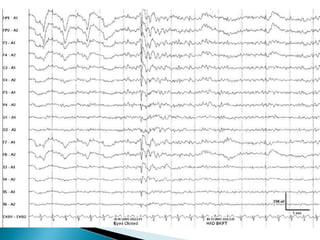

 Beta activity is more abundantly expressed by

medication in children than in adults and with

acute rather than chronic administration.

 Barbiturates and Benzodiazepines

 Cocaine, amphetamines, and

methylphenidate as well as tricyclic

antidepressants

 Withdrawal from alcohol and barbiturates

(G. Bauer and R. Bauer, 2005; Van Cott and Brenner, 2003)

 Beta activityis more abundantly expressed by medication in children than in adults and with acute rather than chronic administration.  Barbiturates and Benzodiazepines  Cocaine, amphetamines, and methylphenidate as well as tricyclic antidepressants  Withdrawal from alcohol and barbiturates (G. Bauer and R. Bauer, 2005; Van Cott and Brenner, 2003)